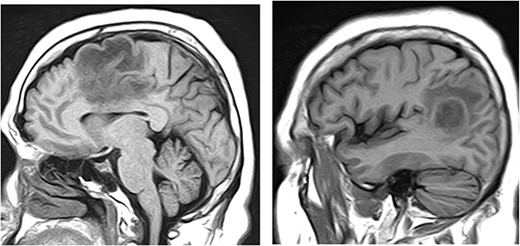

Magnetic resonance imaging (MRI) of brain, with and without contrast, identified four enhancing lesions, concerning for intracranial metastatic disease, located in the right temporal, occipital and frontal lobes (Fig. 1), as well as one in the right cerebellum. The largest mass was in the right cerebellum and measured approximately 3 cm × 2.7 cm. There was associated edema throughout the right occipital and temporal lobes without significant mass-effect or midline shift. The patient’s chest, abdomen and pelvis CT were negative for any malignancy. Neurosurgery was consulted to perform a brain lesion biopsy.

MRI of brain, with and without contrast, identified four enhancing lesions, concerning for intracranial metastatic disease, located in the right temporal (left), occipital (center) and frontal lobes (right).